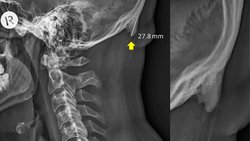

Söz konusu kemik uzantısını ortaya çıkaran veriler, 3 yıldır boyunca Avustralya'nın Queensland bölgesinde çekilen X-ışını taramalarından geliyor. Bu taramalarda, söz konusu çıkıntıların da bulunduğu bölgenin fotoğrafları çekildi. Normalde bu kemik uzantıları çok şaşırtıcı değil ve yaşlılarda görülüyor; çünkü yıllar yılı hayatta kalıp, boyun kaslarına yük bindirince, bu kemikler de ilerleyen yaşlarda gelişebiliyor. Ancak şaşırtıcı olan, genç yetişkinlerde de bu kemiklerin gözükmeye başlamış olması. Hem de kimi zaman bu genç yetişkinlerde yaşlılardan bile daha uzun kemikler görülüyor!

Aynı araştırmacılar, 2016 yılında Journal of Anatomy dergisinde yayınladıkları makalede, 18-30 yaş arası 218 kişiye ait X-ışını taraması fotoğrafını analiz ederek bu kemik büyümesinin genç yetişkinlerin %41'inde görüldüğünü tespit etmişlerdi. Bu kemikler, erkeklerde kadınlara göre daha belirgindi.

Genişlemiş dış oksipital çıkıklık (İng: external occipital protuberance) adı verilen bu durum eskiden gençlerde çok nadiren görülmekteydi. Ancak 2018 yılında Clinical Biomechanics dergisinde yayımlanan bir çalışma, bunun gençlerde daha sık görülmeye başlandığını ve sebebinin genetik veya enflamasyon gibi faktörler olmadığını; daha ziyade mekanik yük binmesi sonucu olduğunu gösterdi.

İşte bundan yola çıkan araştırmacılar, nihayetinde 18-86 yaş arası insanlara ait 1200 X-ışını taramasını inceleyerek, bu kemiklerin popülasyonun %33'ünde bulunduğunu ve şaşırtıcı bir şekilde artık yaş ilerledikçe bu kemiklerin kısaldığını gösterdiler! Bu keşif, yerleşik bilimsel bilgilerimizle fazlasıyla zıt. Çünkü normalde bu çıkıntılı kemiklerin ilerleyen yaşlarda daha da uzadığı düşünülmekteydi! Shahar şöyle diyor: